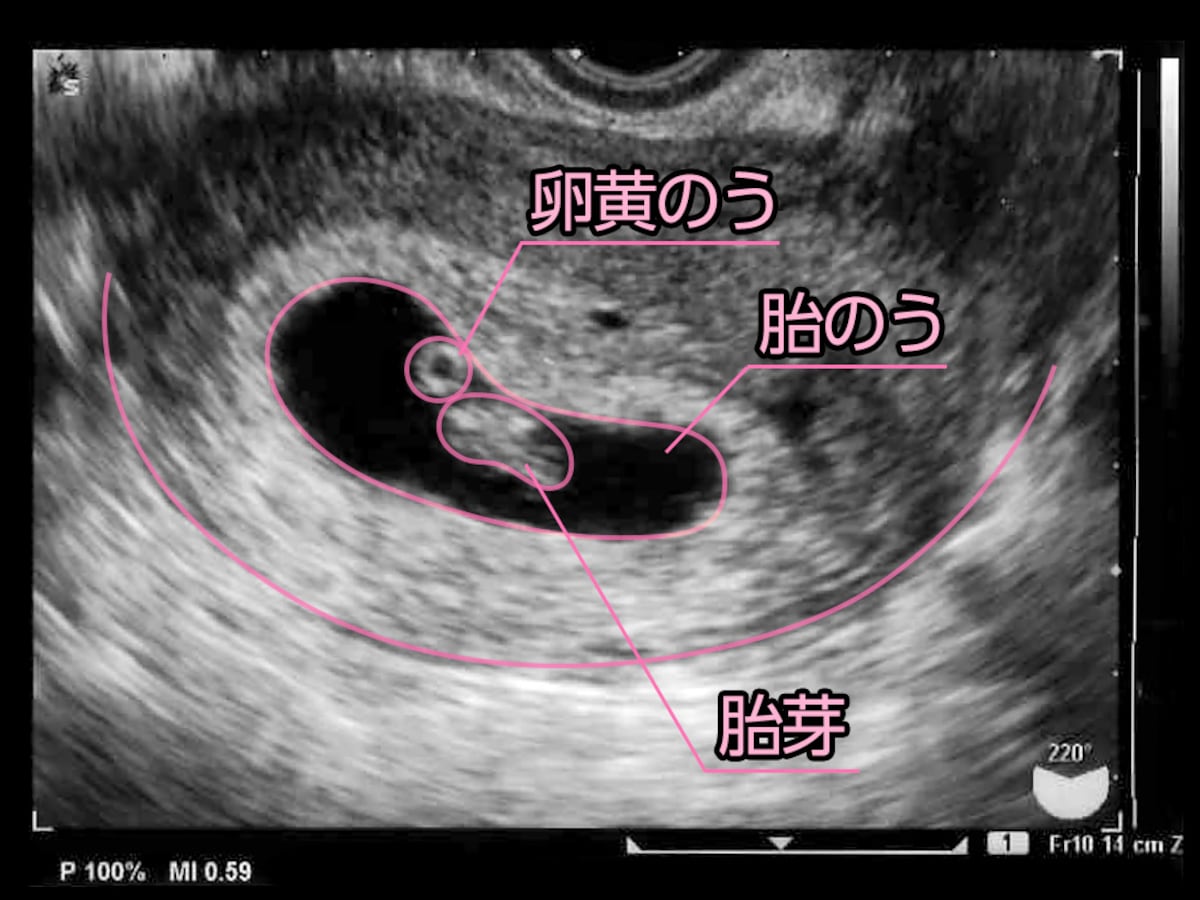

胎嚢や胎芽が見えない原因は 妊娠初期の不安解決 妊活 妊娠ブログ 初めてママ応援隊

妊娠7週目 胎芽 胎嚢のエコー写真や大きさ つわりや流産 妊娠初期 All About

妊娠2ヶ月 妊娠4週 5週 6週 7週 妊娠初期 のおなかの赤ちゃんの様子 妊娠 出産 育児に関する総合情報サイト ベビカム